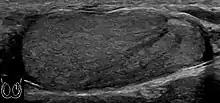

|  Sonography of a normal testis. The normal testis presents as a structure having homogeneous, medium level, granular echotexture. The mediastinum testis appears as the

hyperechoic region located at the periphery of the testis as seen in this figure. | |

The normal adult testis is an ovoid structure measuring 3 cm in anterior-posterior dimension, 2–4 cm in width, and 3–5 cm in length. The weight of each testis normally ranges from 12.5 to 19 g. Both the sizes and weights of the testes normally decrease with age. At ultrasound, the normal testis has a homogeneous, medium-level, granular echotexture. The testicle is surrounded by a dense white fibrous capsule, the tunica albuginea, which is often not visualized in the absence of intrascrotal fluid. However, the tunica is often seen as an echogenic structure where it invaginates into the testis to form the mediastinum testis. In the testis, the seminiferous tubules converge to form the rete testes, which is located in the mediastinum testis. The rete testis connects to the epididymal head via the efferent ductules. The epididymis is located posterolateral to the testis and measures 6–7 cm in length. At sonography, the epididymis is normally iso- or slightly hyperechoic to the normal testis and its echo texture may be coarser. The head is the largest and most easily identified portion of the epididymis. It is located superolateral to the upper pole of the testicle and is often seen on paramedian views of the testis. The normal epididymal body and tail are smaller and more variable in position.